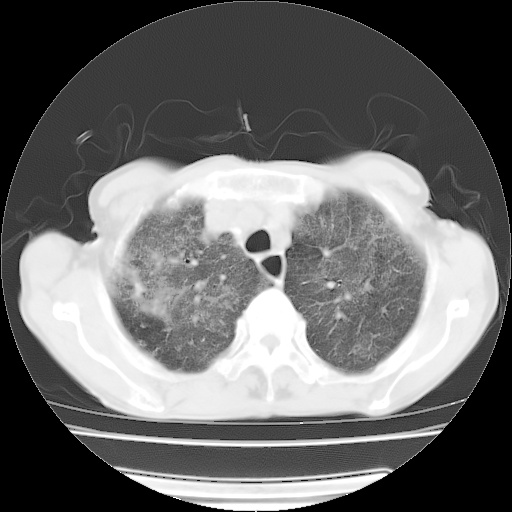

病人发热、气促就诊。原二周前已行ct扫描,当时诊断为双肺下叶、右肺中叶支气管扩张并感染,双肺上叶片状渗出性病变。今天复查胸部ct,双肺下叶支气管扩张并感染病灶较前明显吸收,但双肺上叶渗出性病变较范围较前明显增大。

双肺多发大片状、斑片状高密度渗出影,部分实变,考虑病毒性肺炎。